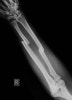

반드시 주관절 및 수근 관절이 반드시 포함되게 촬영합니다.

X-ray만으로도 쉽게 진단할 수 있습니다.

X-ray : 전완골 동시 골절(Both forearm bones fracture)